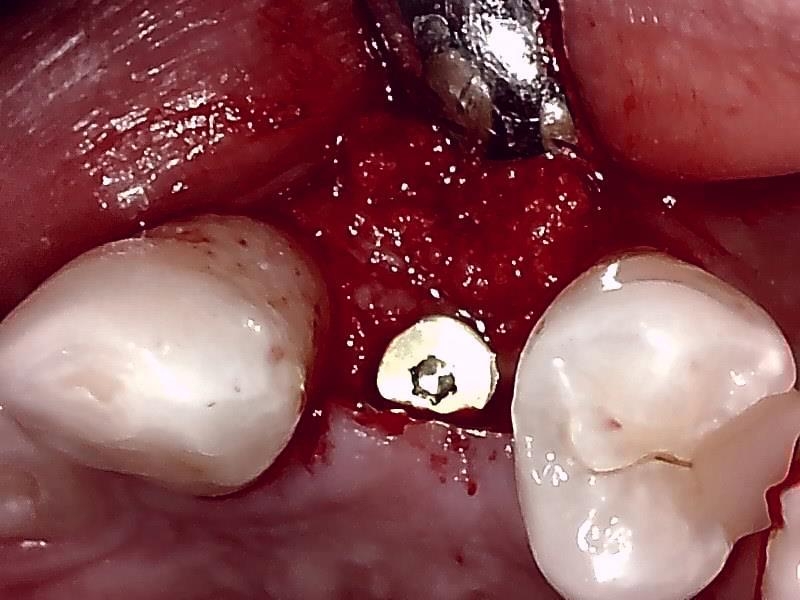

インプラント体の埋入

ヒーリングアバットメント装着

インプラント埋入した状態は良好です。